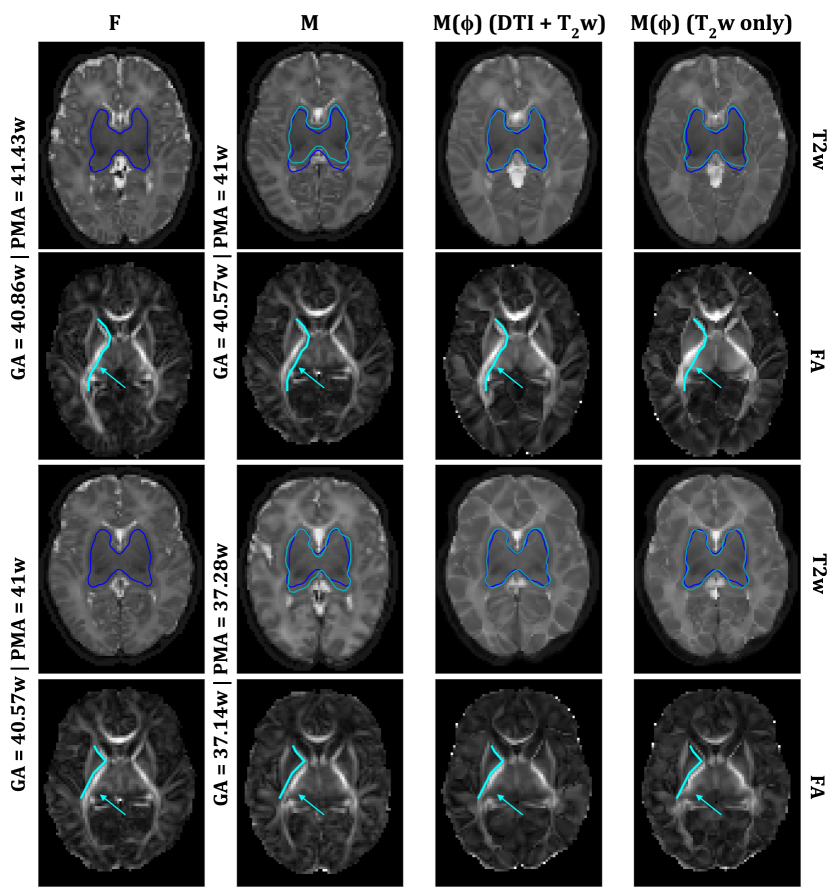

Finally, FigureΒ 4 shows two example registrations. The target images are from two term-born infants with GA = 40.86 weeks and PMA = 41.43 weeks, and GA = 40.57w and PMA = 41w, respectively, while the moving images are from infants with GA = 40.57 weeks and PMA = 41 weeks, and GA = 37.14w and PMA = 37.28w, respectively. The figure shows both \act2w and FA maps of axial slices of the fixed (first column), the moving (second column) and the warped images by our proposed method (third column) and the baseline method (fourth column), respectively. The moved FA maps show that by using \acdti data to drive the learning process of a deep learning registration framework, we were able to achieve good alignment not only on the structural data, but also on the diffusion data as well.

Refer to caption

Figure 4: First two rows show an example registration between a neonate with GA = 40.57w and PMA = 41w as moving, and one with GA = 40.86w and PMA = 41.43w as fixed, last two rows show an example where the moving image is from a neonate with GA = 37.14w and PMA = 37.28w, and fixed is a neonate with GA = 40.57w and PMA = 41w. First column shows axial slices of the fixed \act2w images and FA maps, the second column shows axial slices of the moving \act2w images and FA maps, and the third and fourth columns show the moved images using our proposed network and the baseline network, respectively. In the \act2w maps the deep gray matter (dGM) labels are shown for the fixed images in dark blue and for the moving and moved in cyan. In both cases a higher dGM Dice score was obtained for the \act2w+\acdti model (0.88 and 0.88, respectively), than when using \act2w-only (0.84 and 0.87, respectively). The arrows point at areas where the underlying anatomy was better preserved when using \act2w+\acdti, than when using \act2w-only.